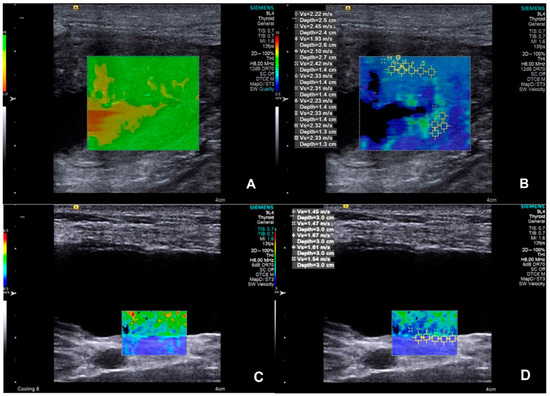

| Variable | Group | Median ± IQR | p-Value | Cut-Off Value |

|---|---|---|---|---|

| SWV of the bladder wall (m/s) | CON | 1.41 ± 0.50 | 0.0045 | >1.585 |

| UTC | 2.53 ± 2.11 | |||

| Sensitivity (%) | Specificity (%) | Likelihood ratio | AUC | |

| 100.0 | 88.89 | 9.000 | 0.984 | |

| Bladder wall thickness (cm) | Group | Median ± IQR | p-value | Cut-off value |

| CON | 0.14 ± 0.26 | 0.0003 | >0.165 | |

| UTC | 0.28 ± 0.05 | |||

| 85.71 | 87.50 | 6.857 | 0.919 |